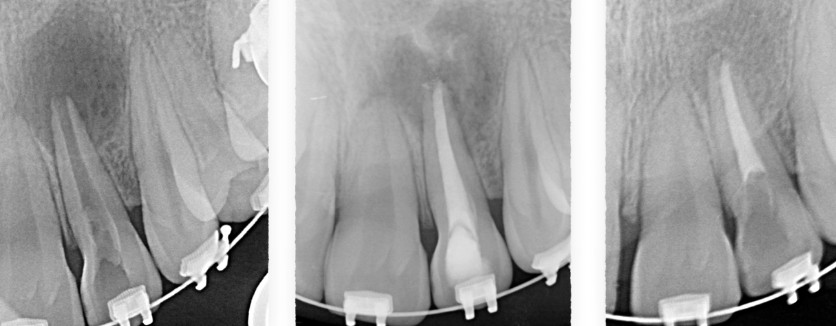

La cirugía endodóntica se puede usar para localizar fracturas o canales ocultos que no aparecen en las radiografías pero que aún manifiestan dolor en el diente. Las superficies radiculares dañadas o el hueso circundante también pueden tratarse con este procedimiento.